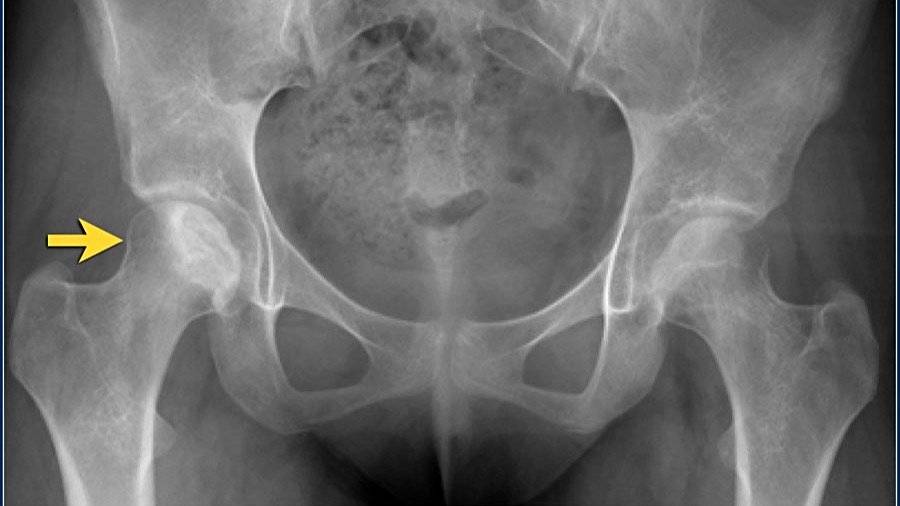

Radyografi

Avasküler Nekroz'un erken evrelerinde düz radyografik bulgular dikkat çekici değildir. Bununla birlikte, Amerikan Radyoloji Koleji, kalça ağrısı ile başvuran Avasküler Nekroz riski taşıyan hastalarda pelvis röntgenini en uygun başlangıç görüntüleme çalışması olarak görmektedir. Bu projeksiyonlardan sadece birinde eklem çökmesi veya kortikal çöküntü görülebileceğinden, hem pelvisin ön-arka görünümü hem de kalçanın kurbağa bacağı lateral görünümü gereklidir.

Hafif-orta Avasküler Nekroz'da radyografiler skleroz ve kemik yoğunluğundaki değişiklikleri gösterir. İlerlemiş hastalıkta düzleşme, subkondral radyolüsent çizgiler (hilal işareti) ve femur başının çökmesi gibi kemik deformiteleri belirgindir.

- Radyografik bulgular subkondral lusensi (hilal işareti) ve subkondral çökmeyi içerir,